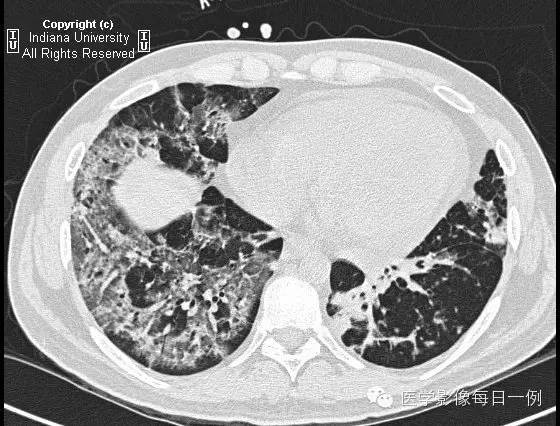

胸部CT示弥漫性肺泡透光度减低,主要位于右肺下叶和左肺上叶,呈铺路石样改变。胸膜无渗出。

【鉴别诊断】(铺路石征)

卡氏肺囊虫肺炎

肺水肿

肺泡蛋白沉积症

肺泡性出血

【诊断】Alveolar hemorrhage